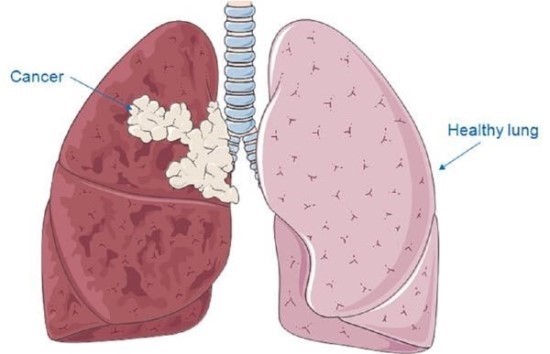

폐 암세포가 기관지까지 퍼지게 되면 점막이 손상되면서 피가 섞인 가래가 자주 발생하기도 합니다.. 이는 폐암 초기증상 뿐 아니라 이미 진행이 많이 된 상태에서도 계속 나타나므로 피 섞인 가래가 보인다면 가볍게 생각하지 말고 즉시 내원해 검사를 받아 보길 바란다.

9. 기침과 가래가 지속됩니다.

감기에 걸린 것도 아니고, 몸이 으슬으슬 춥지 않는데 계속하여 기침과 가래가 들끓는다면 폐암 초기 증상을 의심해 봐야 합니다..